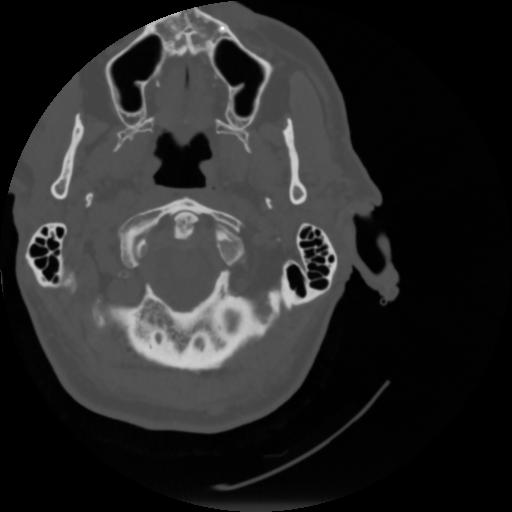

4 CEREBRO,,Vol,0.5,CEREBRO,,